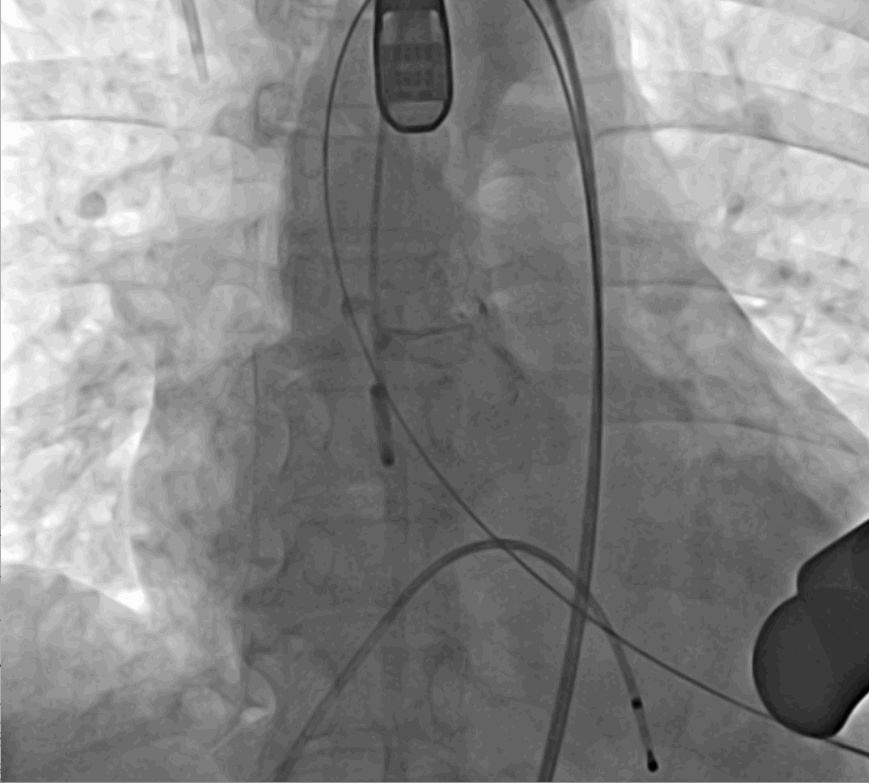

術(shù)前DSA影像圖

手術(shù)采用經(jīng)心尖入路,對患者進行全麻后,在左側(cè)心尖處做3-4cm微創(chuàng)手術(shù)切口,在DSA及超聲引導(dǎo)下手術(shù)順利完成。從導(dǎo)入器械到完成瓣膜置入,僅耗時約10分鐘。術(shù)后即刻主動脈瓣返流程度由術(shù)前大量返流轉(zhuǎn)為消失,患者于導(dǎo)管室拔除氣管插管,次日由ICU轉(zhuǎn)入普通病房。